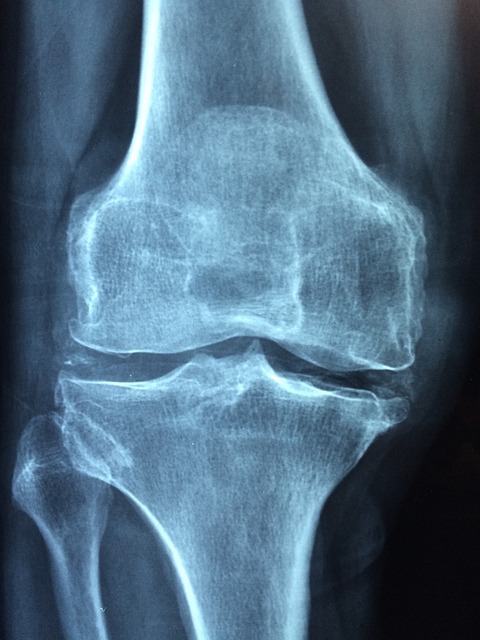

특히 퇴행성관절염은 나이가 들면서 뼈와 근육, 인대가 퇴행화되면서 기능이 손상되고 염증이 일어나 통증이 발생하는 질환인데요 이런 경우 전문의사의 진료와 처방이 필요합니다.

전문 의료진이 평가하는 퇴행성관절염의 자세한 정보는 글 아래서 확인하실 수 있습니다.